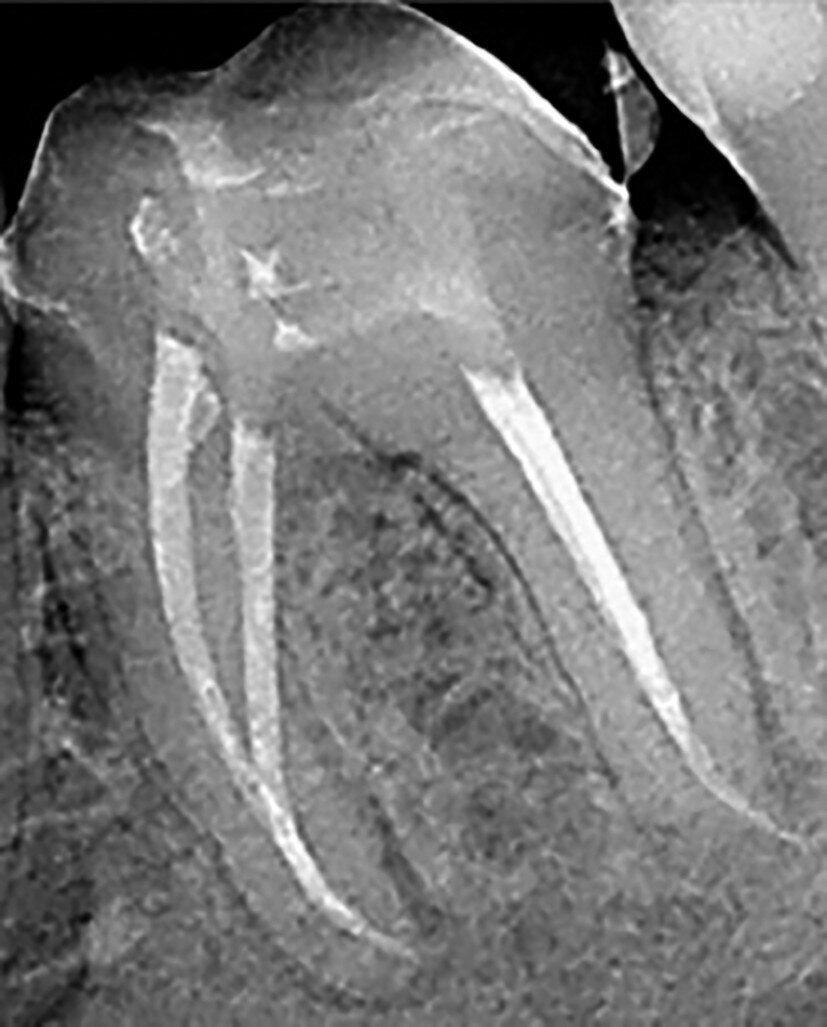

Figs. 12a–d : Depuis la gauche : Cas de l’auteur : dent

37 présentant une fracture radiculaire ; cette dent

montée dans un modèle en plâtre-pierre après extraction,

avec impression du guide de forage CTGEA

monté et du premier foret en place ; les deux

petits orifices d’accès préparés au moyen du guide

de forage ; et la radiographie postopératoire montrant

l’adaptation des cônes dans les canaux après leur négociation et leur mise en forme.